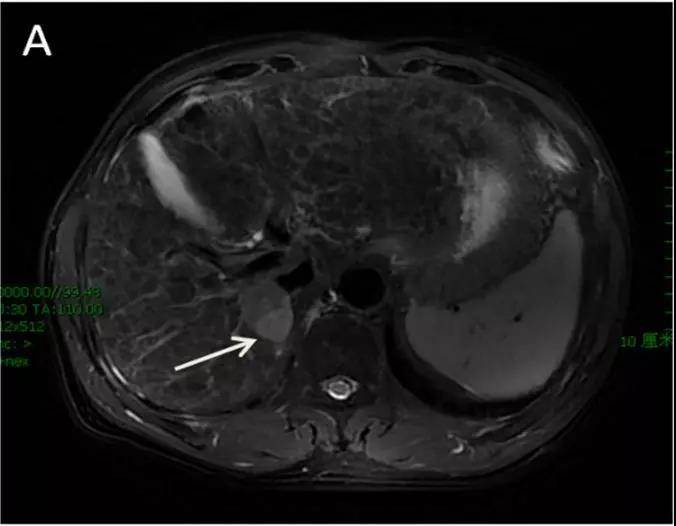

图1 治疗前肿瘤大小3.3 cm×2.4 cm

注:图1~2 为笔者所在单位1例不可手术的HCC患者,采用SBRT技术进行治疗,单次放疗剂量10 Gy,共5次,3个月后复查肿瘤达CR。